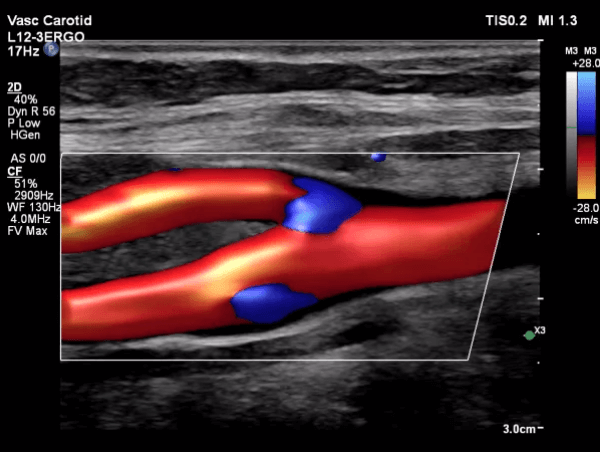

Carotid Artery Ultrasound

Dr. Ghalichi personally performs carotid artery ultrasounds using the state-of-the-art Philips EPIQ Elite (Netherlands) system equipped with AI tools.

• Operator-Dependent Expertise: Benefit from Dr. Ghalichi's specialized skills in conducting and interpreting the ultrasound.

• Intima-Media Thickness (IMT) Measurement: Accurate assessment of the thickness of your arterial walls.

• Radiation-Free Imaging: Safe and painless procedure with no exposure to radiation.

• Trackable Results: Monitor changes in IMT over time to evaluate the effectiveness of treatment strategies.

Carotid Artery Image